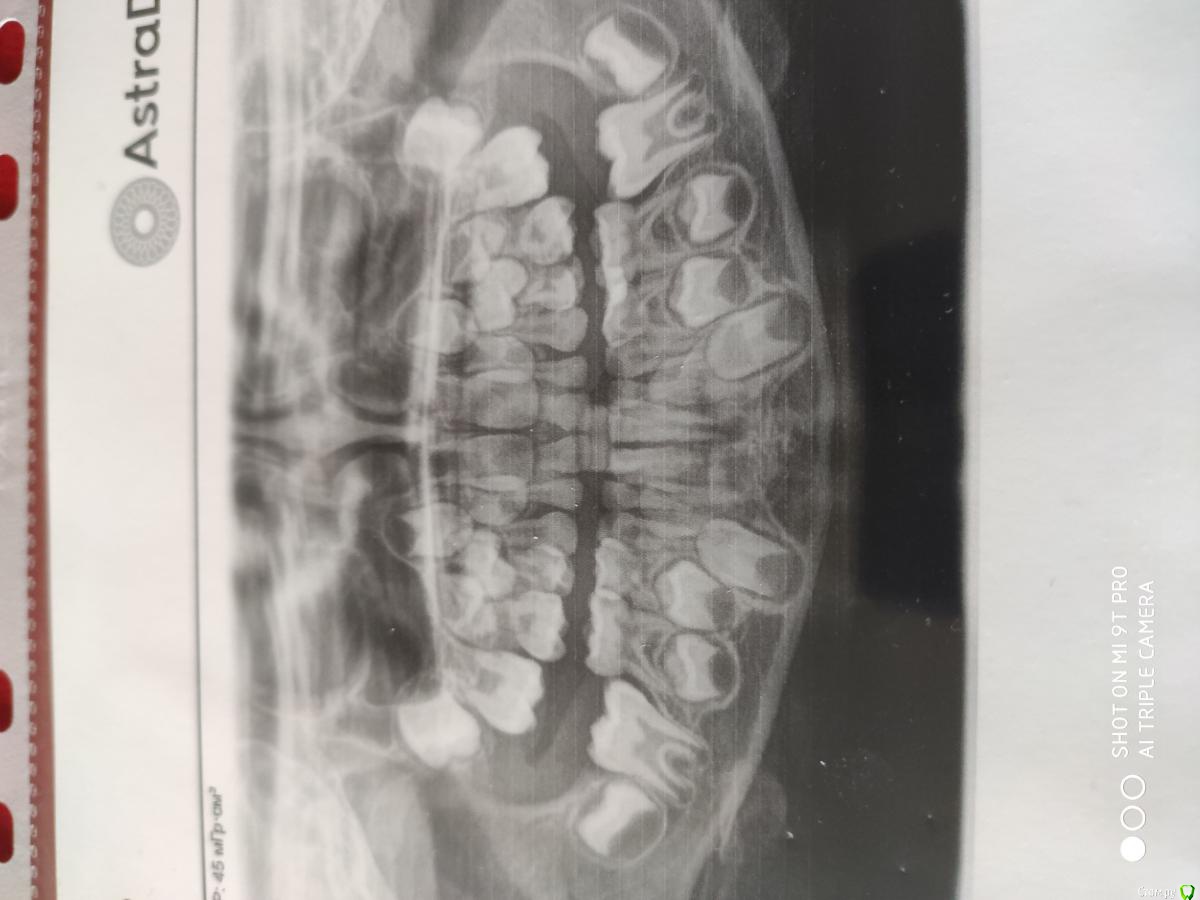

Ирина2511 Опубликовано 5 мая, 2020 Поделиться Опубликовано 5 мая, 2020 (изменено) Здравствуйте. Ребенку 6 лет и 9 месяцев. Начал жаловаться на боль в десне. При осмотре заметила покраснение и припухлость на десне и кариозную полость в зубе. Самочувствие в целом хорошее. Обратились к врачу, сделали снимок. Ответить флюс это или нет врач не смогла. Зуб живой, гноя нет. Поэтому решено было попробовать зуб спасти. Но врач сказала, что гарантии нету т.к корень начал рассасываться. Но добавила, что надо пытаться максимально сохранить все зубы, потому что смены верхних передних ещё не было. Прилагаю фото снимка и самой десны.Подскажите, есть ли смысл бороться за молочный зуб? Флюс это или не флюс? Изменено 5 мая, 2020 пользователем Ирина2511 Ссылка на комментарий